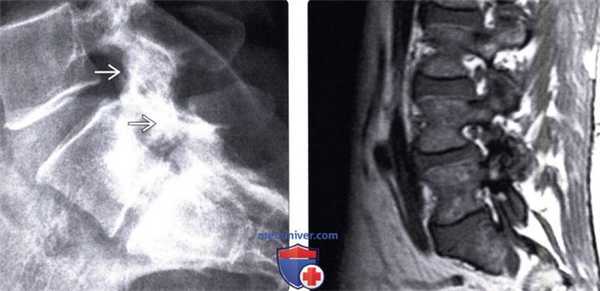

(Слева) Аксиальный срез, Т1-ВИ FS с КУ: признаки накапливающей контраст паравертебральной флегмоны. Также видна эпидуральная флегмона, цирку-лярно окружающая дуральный мешок и сдавливающая его. Определяются признаки двустороннего септического артрита дугоотростчатых суставов, сочетающегося со спондилодисцитом. Путем инфицирования в данном случаее стал гематогенный путь, а источником — флегмона нижней конечности.

(Справа) Сагиттальный срез, Т1-ВИ, FS с КУ: признаки правостороннего септического артрита дугоотростчатого сустава L5-S1. Периартикулярный воспалительный процесс распространяется в правое межпозвонковое отверстие. Правый боковой заворот спинномозгового канала на уровне S1 сужен за счет эпидуральной флегмоны. (Слева) Рентгенография в прямой проекции: признаки правостороннего фокального сколиоза на уровне грудопоясничного перехода. Здесь отмечается снижение высоты межпозвонкового диска и формирование спондилофитов на вогнутой стороне деформации.